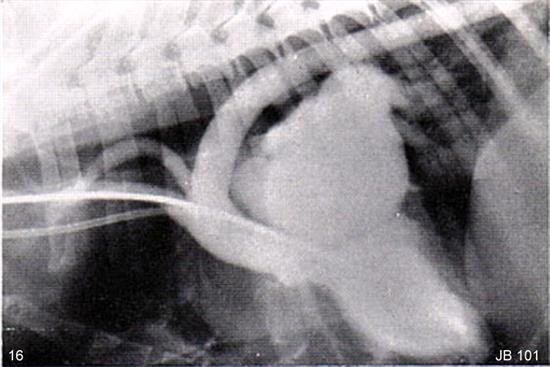

Figure 16

Click

here to see the answer.